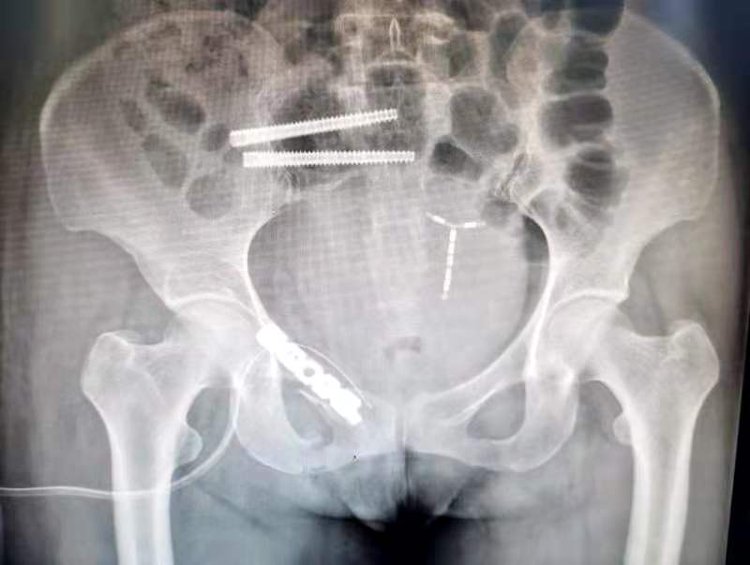

术中,骨科机器人机械臂完美解决了传统骨科手术“看不见、打不准、拿不稳”三大难题,让骨科手术更快更完美。本次手术耗时约30分钟。刘涛主任通过精准定位及机器人机械臂精确运动,规划螺钉方向及长度,避开髋臼关节面及盆腔内重要脏器、大血管,复位骶髂关节后,准确地将两枚长度85毫米的空心螺钉置入骶髂关节,然后又利用机器人导航,成功快速固定了其他骨折部位,顺利完成骨盆骨折微创内固定手术。

手术切口约1厘米、出血量仅有50毫升,这对于骨盆及骶骨骨折的患者来说,创伤如此微小令人惊叹。小创伤也将极大减轻患者痛苦,加速康复。